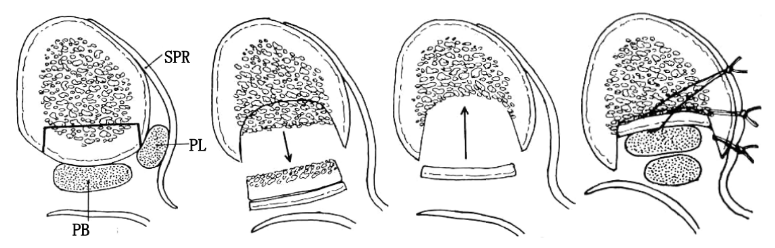

腓骨上支持带(SPR):起于腓骨外侧面和腓骨外踝窝,绕过腓骨肌腱后止于跟骨和跟腱外侧。SPR没有直接牢固固定于纤维软骨脊,而是与腓骨外侧面的骨膜融合。

I型:最常见(51%),腓骨上支持带(SPR)和骨膜仍保持联系,骨膜从外踝上撕脱,腓骨肌腱滑向前方使骨膜和外踝分离。

Ⅱ型:(33%)纤维软骨脊连同腓骨上支持带(SPR)一起和外踝分离,腓骨肌腱向前脱位。

Ⅲ型:(16%)纤维软骨脊连同部分外踝骨质和腓骨上支持带(SPR)一起与外踝分离,肌腱脱位至骨折块下方。

IV型:Oden1987年在此基础上外,还有少见的第IV型,表现为腓骨上支持带(SPR)的完全撕脱或断裂,并且肌腱移位于支持带的外表面。

通过切除腓骨后方部分骨质,可以加深腓骨沟,改变、并增加了腓骨肌腱的稳定。